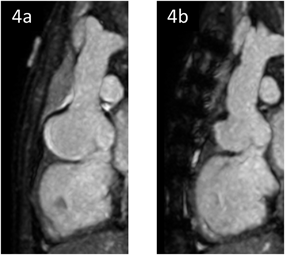

術前・術後MRI検査

術後6カ月のMRI検査では,バルサルバ洞径は術前の48.2 mmから36.9 mmに縮小し,再建した右バルサルバ洞の形態は良好に保たれていた(Fig. 4a, 4b).

Fig. 4 MRI検査

(4a)術前.(4b)術後6カ月.バルサルバ洞径は48.2 mmから36.9 mmに縮小していた.再建した右バルサルバ洞の形態は良好に保たれていた.